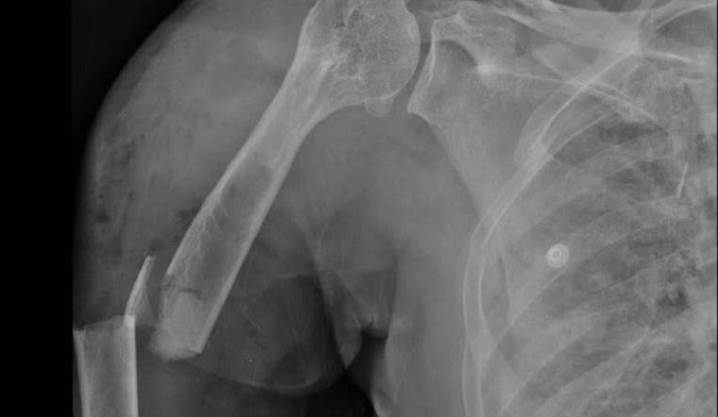

黃婦事發當天做完太空包的工作後,騎機車返家途中,遭一輛小貨車撞上,緊急被送往彰化醫院急診,全身都是傷,右上臂開放性骨折、右側血胸,右鎖骨、肱骨、橈骨、第3至5掌骨、骨盆、脛骨、腓骨,及第6至9節胸椎、胸骨、2側多處肋骨皆出現骨折。

由于血壓持續下降,最低僅62/28 mmHg,因多重創傷與血胸,彰化醫院立即啟動創傷小組,並送入加護病房。

胸腔外科主任林聿騰表示,黃婦光肋骨就斷了21處,血胸、氣胸及胸廓變形,造成嚴重錯位的「連枷胸」,也就是相鄰3根以上的肋骨骨折,恐引發肺炎、呼吸衰竭等併發癥,準備開胸手術時,出現延遲性小腸破裂,指的是小腸並未在第一時間破裂,只得緊急穩住病人呼吸,請外科醫師先進行小腸部分切除手術,再進行胸腔手術。